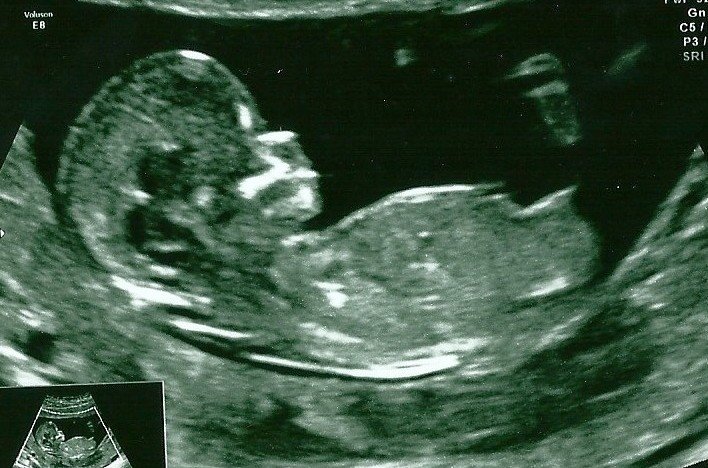

**Update...It's a baby girl!!! We are sooo happy!!!***

Thank you for your guesses! I have a boy and a girl already and both their nub shots were very obvious and clear, whereas this little tinker is really confusing me! lol. I have a real mix of guesses and am desperate to know! (Think the reason I am so obsessed with it is because my hubby does not want to find out at 20 week scan!)

Looks very flat and forked so definitely a girl guess from me!

Girly nub although slightly angled and could still rise hove er the bump at the top makes me think blue......

Ok so here is a different pic from the same 12 week scan....any more thoughts and guesses would be very much appreciated.....I'm thinking boy???Attachment 15382

Super girly. I'm confused as to what looks at all boyish about it. . .Really nubs don't get much flatter than this.

I'm still thinking girl. I think the baby's spine is a bit curved giving the appearance of a 'tilted' nub, but the actual nub is very straight.